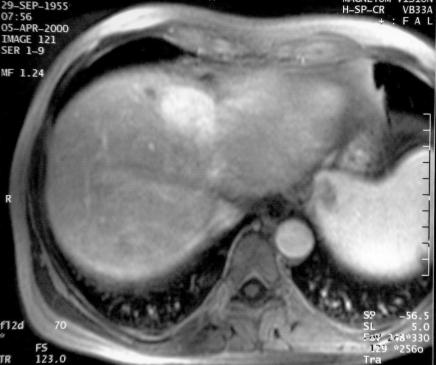

T1 avant gadolinium

T1 gadolinium précoce

T1 gadolinium tardif

Nudule très légèrement hyper T2, Iso T1, se renforçant

au temps artériel précose de 4 cm de diamètre les

contours sont flous. Cette lésion est interprétée

comme une anomalie vasculaire localisée à surveiller compte

tenu de sa taille.

Pondération T2